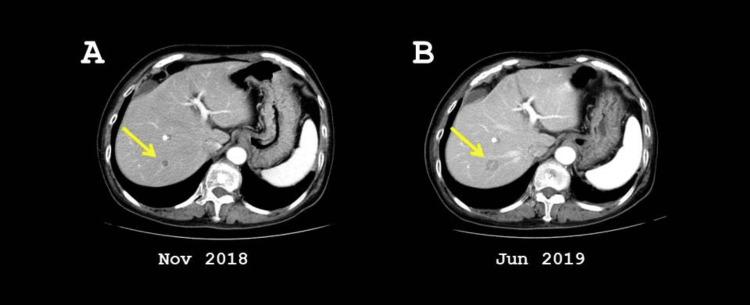

The prognosis of triple-negative breast cancer (TNBC) with hepatic metastasis is generally poor. Here, we report the case of a 70-year-old woman with TNBC whose hepatic metastasis did not recur for more than three years after radiofrequency ablation (RFA). During this period, the patient received chemotherapies with relatively mild side effects, such as eribulin mesylate and gemcitabine, maintaining a good quality of life. Although PARP inhibitors and immune checkpoint inhibitors are now available for TNBC, many cases are not eligible for these treatments due to the absence of specific target molecules. RFA may be a useful option in selected cases of hepatic metastasis from TNBC.

三阴性乳腺癌(TNBC)发生肝转移后的预后通常较差。在此,我们报告一例70岁的TNBC女性患者,其肝转移灶在接受射频消融(RFA)治疗后三年多未复发。在此期间,患者接受了副作用相对较轻的化疗,如甲磺酸艾瑞布林和吉西他滨,维持了良好的生活质量。尽管目前PARP抑制剂和免疫检查点抑制剂可用于TNBC治疗,但由于缺乏特定的靶分子,许多病例不符合这些治疗条件。对于TNBC肝转移的某些特定病例,RFA可能是一种有用的选择。